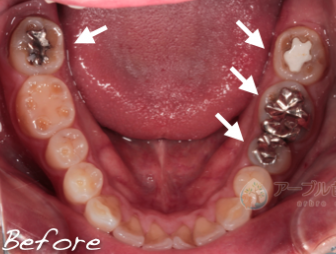

虫歯の治療を受ける場合は、患部の写真を撮って治療してもらえる歯科医院に行くことをオススメしています

当院では治療する場合は、口腔内写真を必ず撮影し、治療前と治療中、治療後で最低3枚以上撮影して、 治療後にどのような状態だったのか写真を撮って説明しています

問題が起きている歯や歯茎を口腔内専用カメラで撮影し治療前と治療後を比較。

治療後にモニターに映して説明しています。

治療途中も虫歯の取り残しがないことを記録で残しているため、治療後に歯に何か気になることがあっても過去の治療内容を見ることができるので安心です。

口腔内写真を取り、患部を拡大することにより、虫歯の取り残しを確実になくししています

以前治療した銀歯の内部から虫歯の取り残しが見つかった症例

最近治療した歯の内部から虫歯が見つかった症例

上記の写真はここまで虫歯になっていても痛みが全くない症例でした

治療を受ける際は、幹部の写真を撮影している歯科医院をお勧めしています

きちんと虫歯を治療しているかどうかはご自身の目で判断することが重要です

治療していると、過去に治療したレジン治療や銀歯治療の内部で虫歯の取り残しが多く見られます

治療を受ける際は、必ず内部で虫歯の取り残しがないかどうか自分の目で確認できる歯科医院を選択することをオススメしています